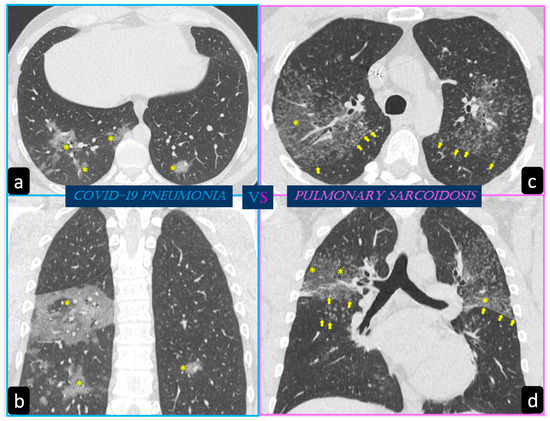

3.2. HRCT Findings of Lung Involvement from COVID-19

Role of HRCT in Discriminating Lung Involvement and the Diffusion of Deep Learning Techniques